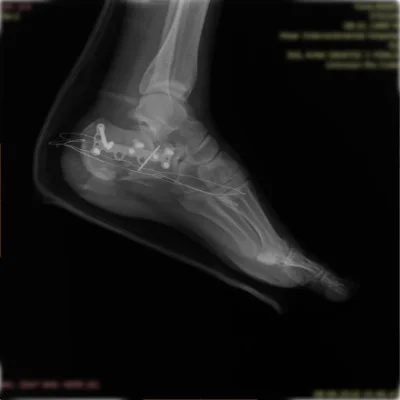

Görüntüleri büyütmek için resmin üstüne tıklayınız.